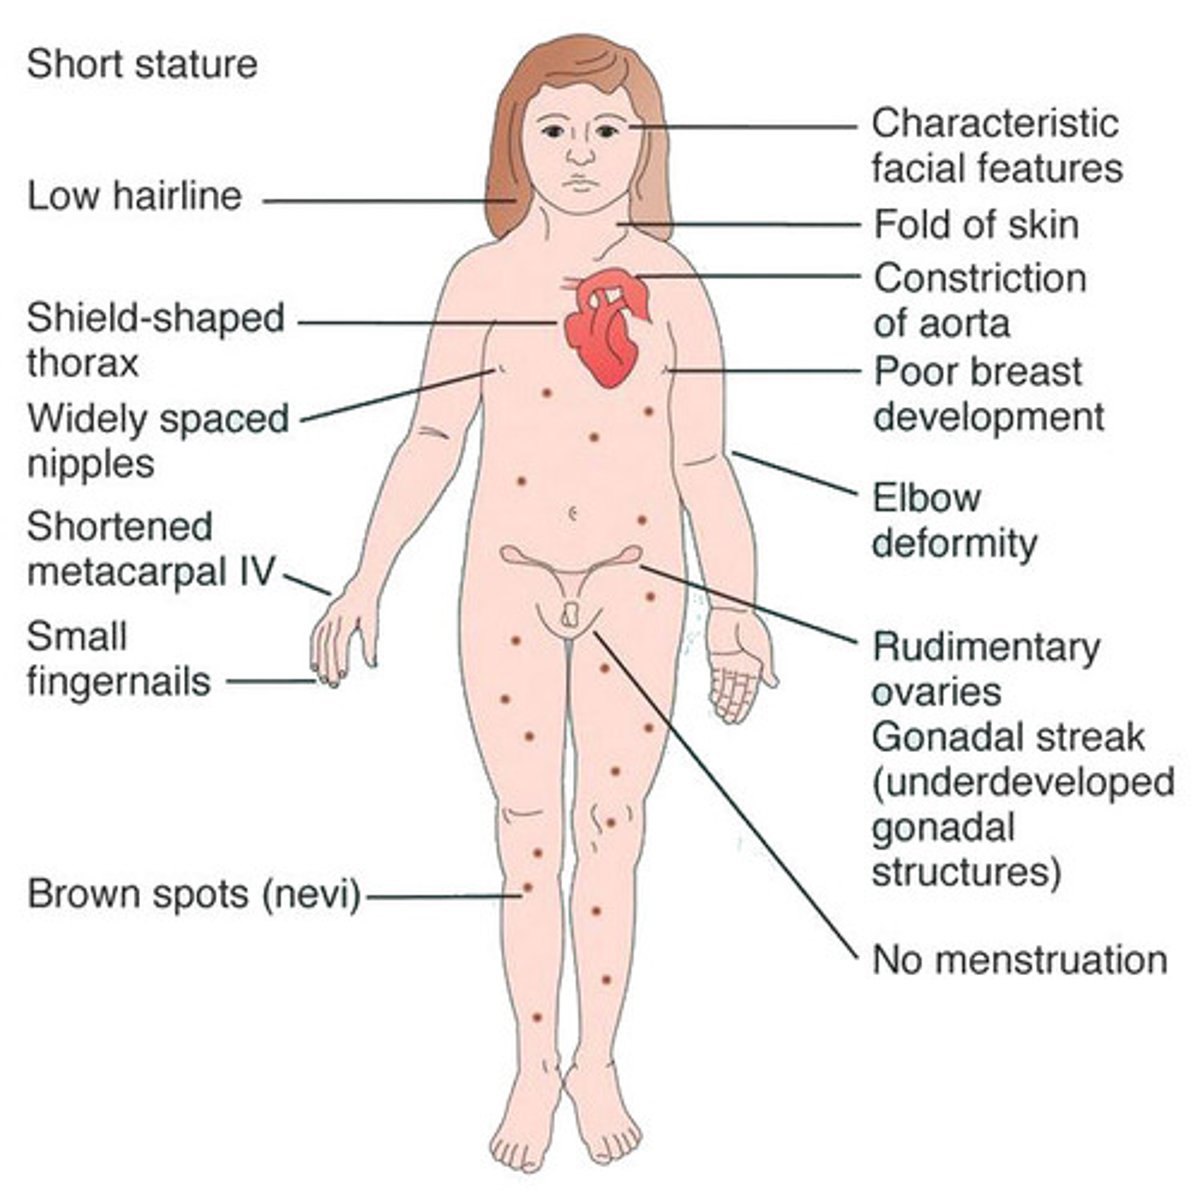

What is the MC sex chromosome disorder in females, resulting in wideset nipples, excessive nuchal skin, & lymphadema?

Turners syndrome

young female presents with underdeveloped breasts & uterus, primary hypogonadism, ovarian dysgenesis and short stature (4.5 feet). What is the probable diagnosis ?

Turner Syndrome (45,X)

paternal absence of X